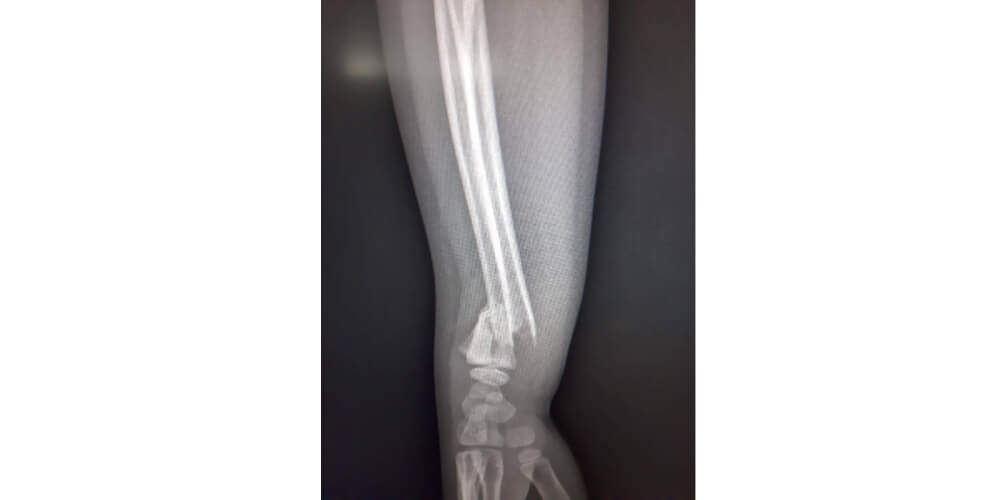

Овај рендгенски снимак показује дислоцирану дисталну фрактуру подлактице која захвата дистални радијус, са пратећим захваћеношћу улнарне кости близу зглоба - акутну трауматску повреду која узрокује значајан бол и функционално оштећење које захтева хитну ортопедску процену, репозицију и имобилизацију.

Пре донације SAMA-е, овај пацијент би био приморан да трпи значајне болове и путује више од сат времена до Требиња ради дијагнозе и лечења. Данас, захваљујући подршци SAMA-е, повреда је дијагностикована и одмах лечена - локално у Гацку, на лицу места.